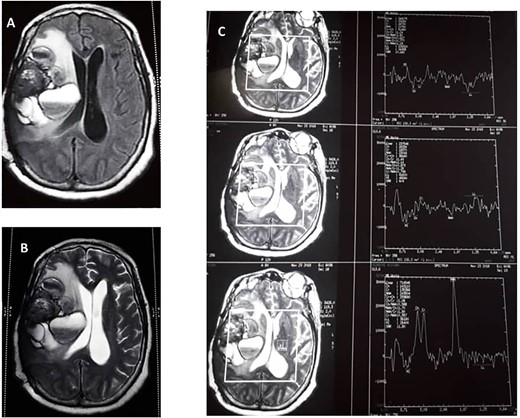

Cranial magnetic resonance image (MRI) revealed a large heterogeneous solid mass with multiple cystic areas in the right parietal lobe; this was associated with marked mass effect (Fig. 1A and B). The total brain lesion measured 7.2 × 6.0 × 7.3 cm, with the solid lateral component measuring 2.9 × 2.8 × 4.1 cm. There was heterogeneous contrast enhancement with extensive perilesional oedema. Magnetic resonance spectroscopy revealed decrease N-acetyl aspartate, creatinine and myoinositol and markedly increased lactate (Fig. 1C).

(A) Preoperative T1 weight. (B) T2-weighted MRIs. (C) Preoperative magnetic resonance spectroscopy.